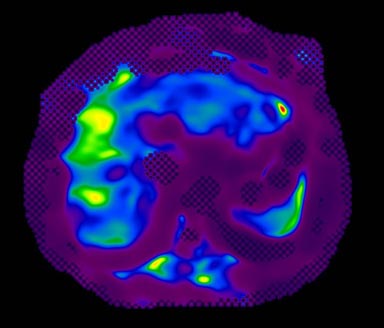

MR-Touch acquisition generates the following image types: magnitude, phase maps, wave maps, and an attenuation map. Six relative stiffness images are reconstructed for each slice location. The relative stiffness images are reconstructed in color and grey scale, and in masked and un-masked versions. Mask portion is depicted as a checkerboard pattern on the image. It is created to identify regions that should not be included in ROI measurements.

Figure 6. Color Elastogram, with mask, scale 0-8K

Figure 8. Color Elastogram, with mask, scale 0-20K